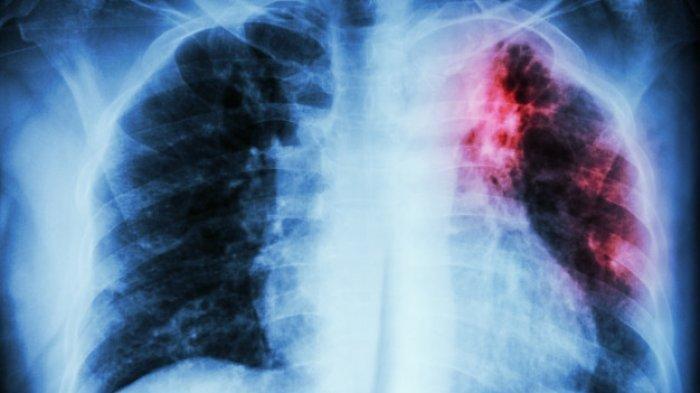

Gejala penyakit TBC yang wajib diwaspadai - 3 Minggu Batuk Berdahak Disertai Darah, Awas Itu Gejala Penyakit TBC Paru, Jangan Diabaikan

Penyakit TBC Paru adalah penyakit menular akibat infeksi bakteri.

TBC umumnya menyerang paru-paru, tetapi juga dapat menyerang organ tubuh lain, seperti ginjal, tulang belakang, dan otak.